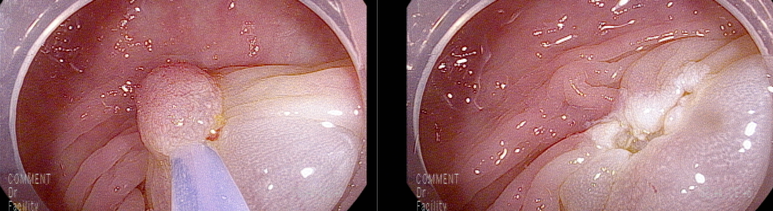

마지막 유경성 거대 용종을 제외하고 점막 소구 패턴(pit pattern)이 불규칙하게 관찰되어(Vi) 고등급의 선종 혹은 점막암을 의심하여 충분히 융기시켜 경계가 확실히 포함되고 한조각으로 완전 절제하기 위해 넓게 절제함

7 mm 크기

19-20 mm 크기의 유경성(목이있는) 용종은 클립을 적절히 사용하여 출혈예방함